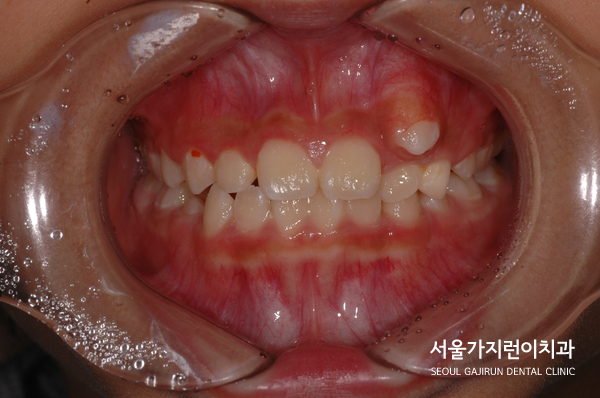

심한 상악 송곳니 덧니의 경우 교정을 할 수 있을까요? 이번 케이스는 어린이 환자분이었습니다. 덧니가 심해 환자와 보호자 모두 이 덧니를 개선하고 싶어했는데요. 아이가 성장 중이었기 때문에 엉뚱한 곳으로 치아가 맹출하지 않도록 신경을 쓴 부분입니다.

치열이 좁아서 공간이 부족하거나 유치가 제때 빠지지 않은 경우에는 '이소맹출'이 발생할 수 있었는데요. 치아의 맹출 방향 이상, 잇몸 혹은 뼈 내부의 병변, 유전적 및 발달적 용인에 의해 발생할 수 있었어요. 어린이 환자의 경우에는 이소맹출 때문에 좌측 유견치의 뿌리가 흡수되지 않았고 동요도 없는 상태였는데요. 골격적으로 봤을 때 하악골의 과성장 패턴도 보이고 있었어요.

그래서 엉뚱한 자리로 자란 상악 좌측 견치를 제 자리로 이동시키기 위해 잔존한 유견치를 발치했고 해당 자리로 이소 맹출된 견치를 이동시키는 플랜을 수립했었습니다. 어금니를 전방으로 이동시키면 견치를 배열할 공간이 줄어들 수 있었는데 환자의 보호자 분께서 미니스크류 사용을 반대하셨기 때문에 다른 방법을 찾아야 했었습니다. 그래서 환자 분의 경우 TPA(횡구개 아치)를 본딩해 어금니가 이동하지 않도록 잡아주었습니다.

송곳니 치아교정을 진행하면서 어금니가 이동하지 않도록 신경 쓴 부분이었는데요. 유치가 빠지고 영구치가 자라는 과정에 있는 성장기 어린이환자였기 때문에 이 부분도 조심스럽게 접근해 진행하였습니다.